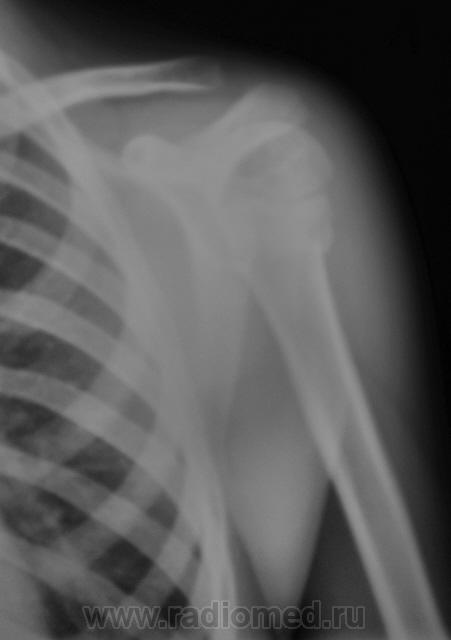

Да, дети разные.

Это у меня нижняя группа снимков не загрузилась - решил верхние - двух человек...

Но у первого пострадавшего помимо перелома и вывиха в плечевом ещё и надрыв/разрыв ключично-акромиального сочленения.

На мой взгляд, вывих спорный.

В обоих случаях перелом хирургической шейки плечевой кости. А почему только в одной проекции? Мы всегда снимаем в двух - в прямой и аксиальной.